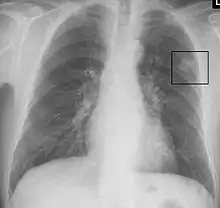

Le cancer du poumon peut être vu sur les radiographies thoraciques et le scanner. Le diagnostic est confirmé par une biopsie. Ceci se fait généralement par bronchoscopie, ou par biopsie guidée par scanner. Le traitement et le pronostic dépendent du type histologique du cancer, de son stade (degré de dissémination), et de l'état général de santé du patient.

La radiographie thoracique est la première mesure à prendre si un patient se plaint de symptômes pouvant suggérer un cancer du poumon. Ceci peut révéler une masse évidente, un élargissement du médiastin (qui suggère une extension aux ganglions lymphatiques qui s'y trouvent), une atélectasie (affaissement), une inflammation (pneumonie) ou un épanchement pleural. En l'absence de signes radiographiques, mais si les soupçons sont élevés (par exemple, un gros fumeur avec hémoptysie), une bronchoscopie ou un scanner peuvent donner l'information nécessaire. La bronchoscopie ou la biopsie guidée par scanner sont souvent utilisées pour identifier le type de tumeur[3].

Le diagnostic différentiel pour les patients qui présentent des anomalies de la radiographie thoracique consiste à distinguer le cancer du poumon des maladies non malignes. Ces dernières peuvent être des infections, telles que la tuberculose ou la pneumonie, ou des inflammations comme la sarcoïdose. Ces maladies peuvent donner lieu à des lymphadénopathies du médiastin, ou à des nodules du poumon, qui peuvent imiter des cancers du poumon[4]. Le cancer du poumon peut par contre être une trouvaille incidentelle : un nodule pulmonaire solitaire (lésion en « pièce de monnaie ») vu sur une radiographie du thorax ou un scanner pris pour une tout autre raison.